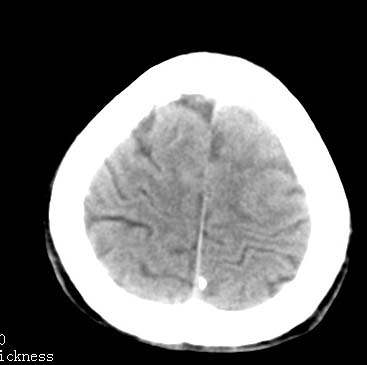

以下是引用卜一在2007-8-29 6:48:00的发言:[br]左侧额叶不均匀密度影,占位效应明显,界限不清。支持:占位性病变,建议增强!

以下是引用clj20在2007-8-29 9:47:00的发言:[br]蛛网膜下腔出血,左侧额叶不均匀密度影,占位效应明显,界限不清。支持:占位性病变,建议增强!

以下是引用xulianj在2007-8-29 20:15:00的发言:[br]蛛网膜下腔出血,左侧额叶不均匀密度影,占位效应明显,界限不清。支持:占位性病变,建议增强!

以下是引用jiangjing在2007-8-29 14:33:00的发言:[br]左侧额叶不均匀密度影[低密度为主,边缘见等密度环环绕]占位效应明显,界限不清。支持:占位性病变,建议增强! [br][br]